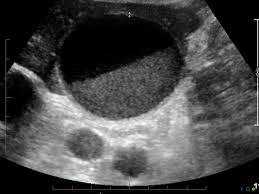

- Dupa cum ii spune sinumele, litiaza biliaraasimptomatica nu da nici un simptom- diagnosticul se pune intamplator prin ecografie